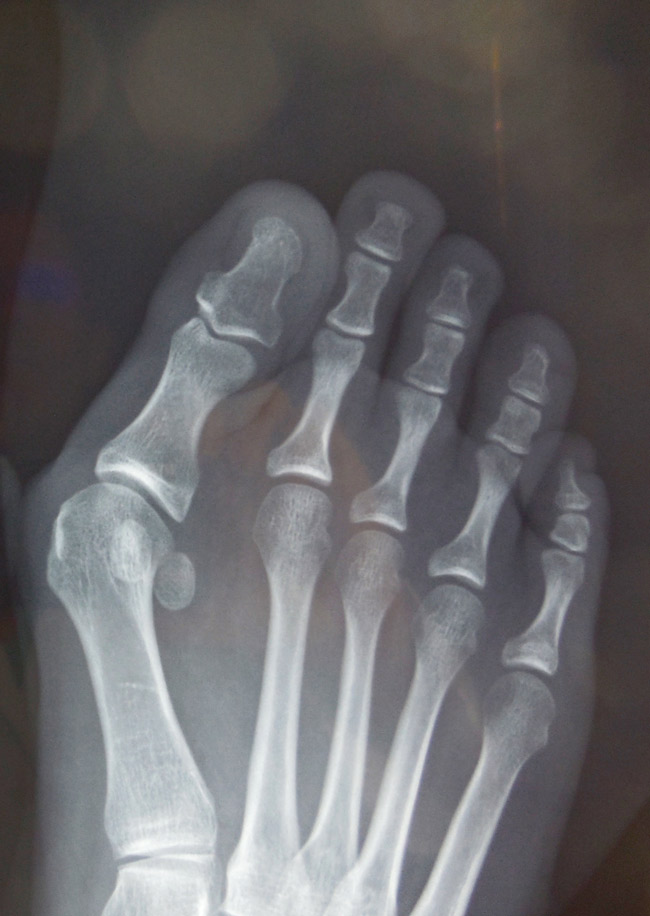

Alluce valgo

Guarda il casoalluce valgo

L’intervento consiste nell’eseguire delle osteotomia correttive (sia con tecnica tradizionale che mini invasiva) che permettono la correzione meccanica del primo raggio ripristinando un corretto allineamento.

Fig. 3 esempio radiografico di alluce valgo prima dell’intervento